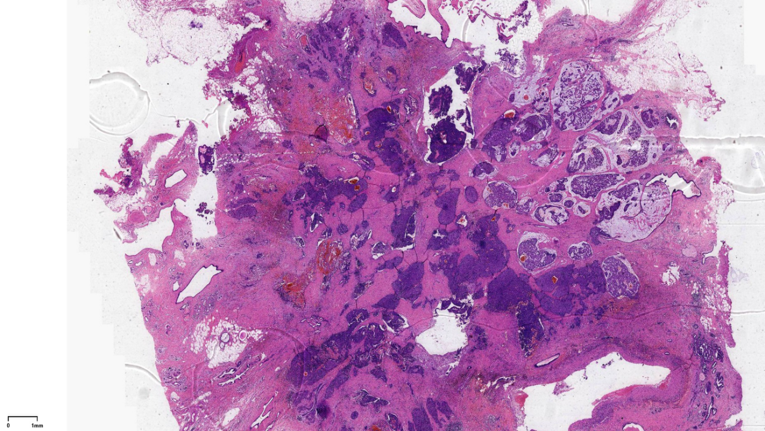

左乳肿物:灰黄色组织一块约5.4*4.1*3.9cm,切面见直径1.9cm的暗红灰白区域,质中,界不清。

最终诊断:浸润性实性乳头状癌,部分为粘液癌。

2、实性乳头状癌伴浸润:轮廓圆滑的结节,伴有浸润性成分,包括粘液癌,NET,浸润性癌(NST)

SPC+富于细胞的黏液癌